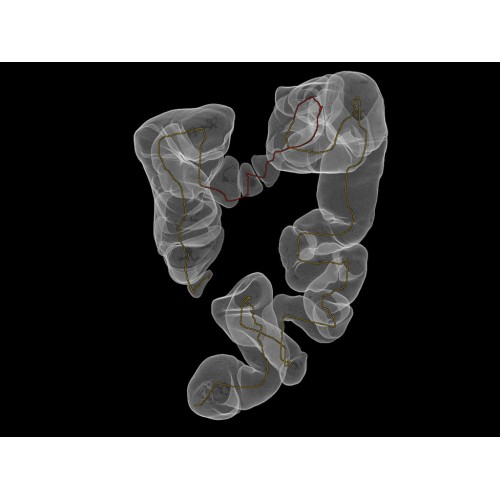

Позволяет проводить комплексные исследования всех анатомических зон, включая нейровизуализацию, ангиографию, исследования органов грудной и брюшной полости. Особенно эффективен для раннего выявления онкологических заболеваний.

Обеспечивает высокую точность при кардиологических исследованиях, визуализации костных структур и суставов. Подходит для динамического наблюдения в ходе лечения.